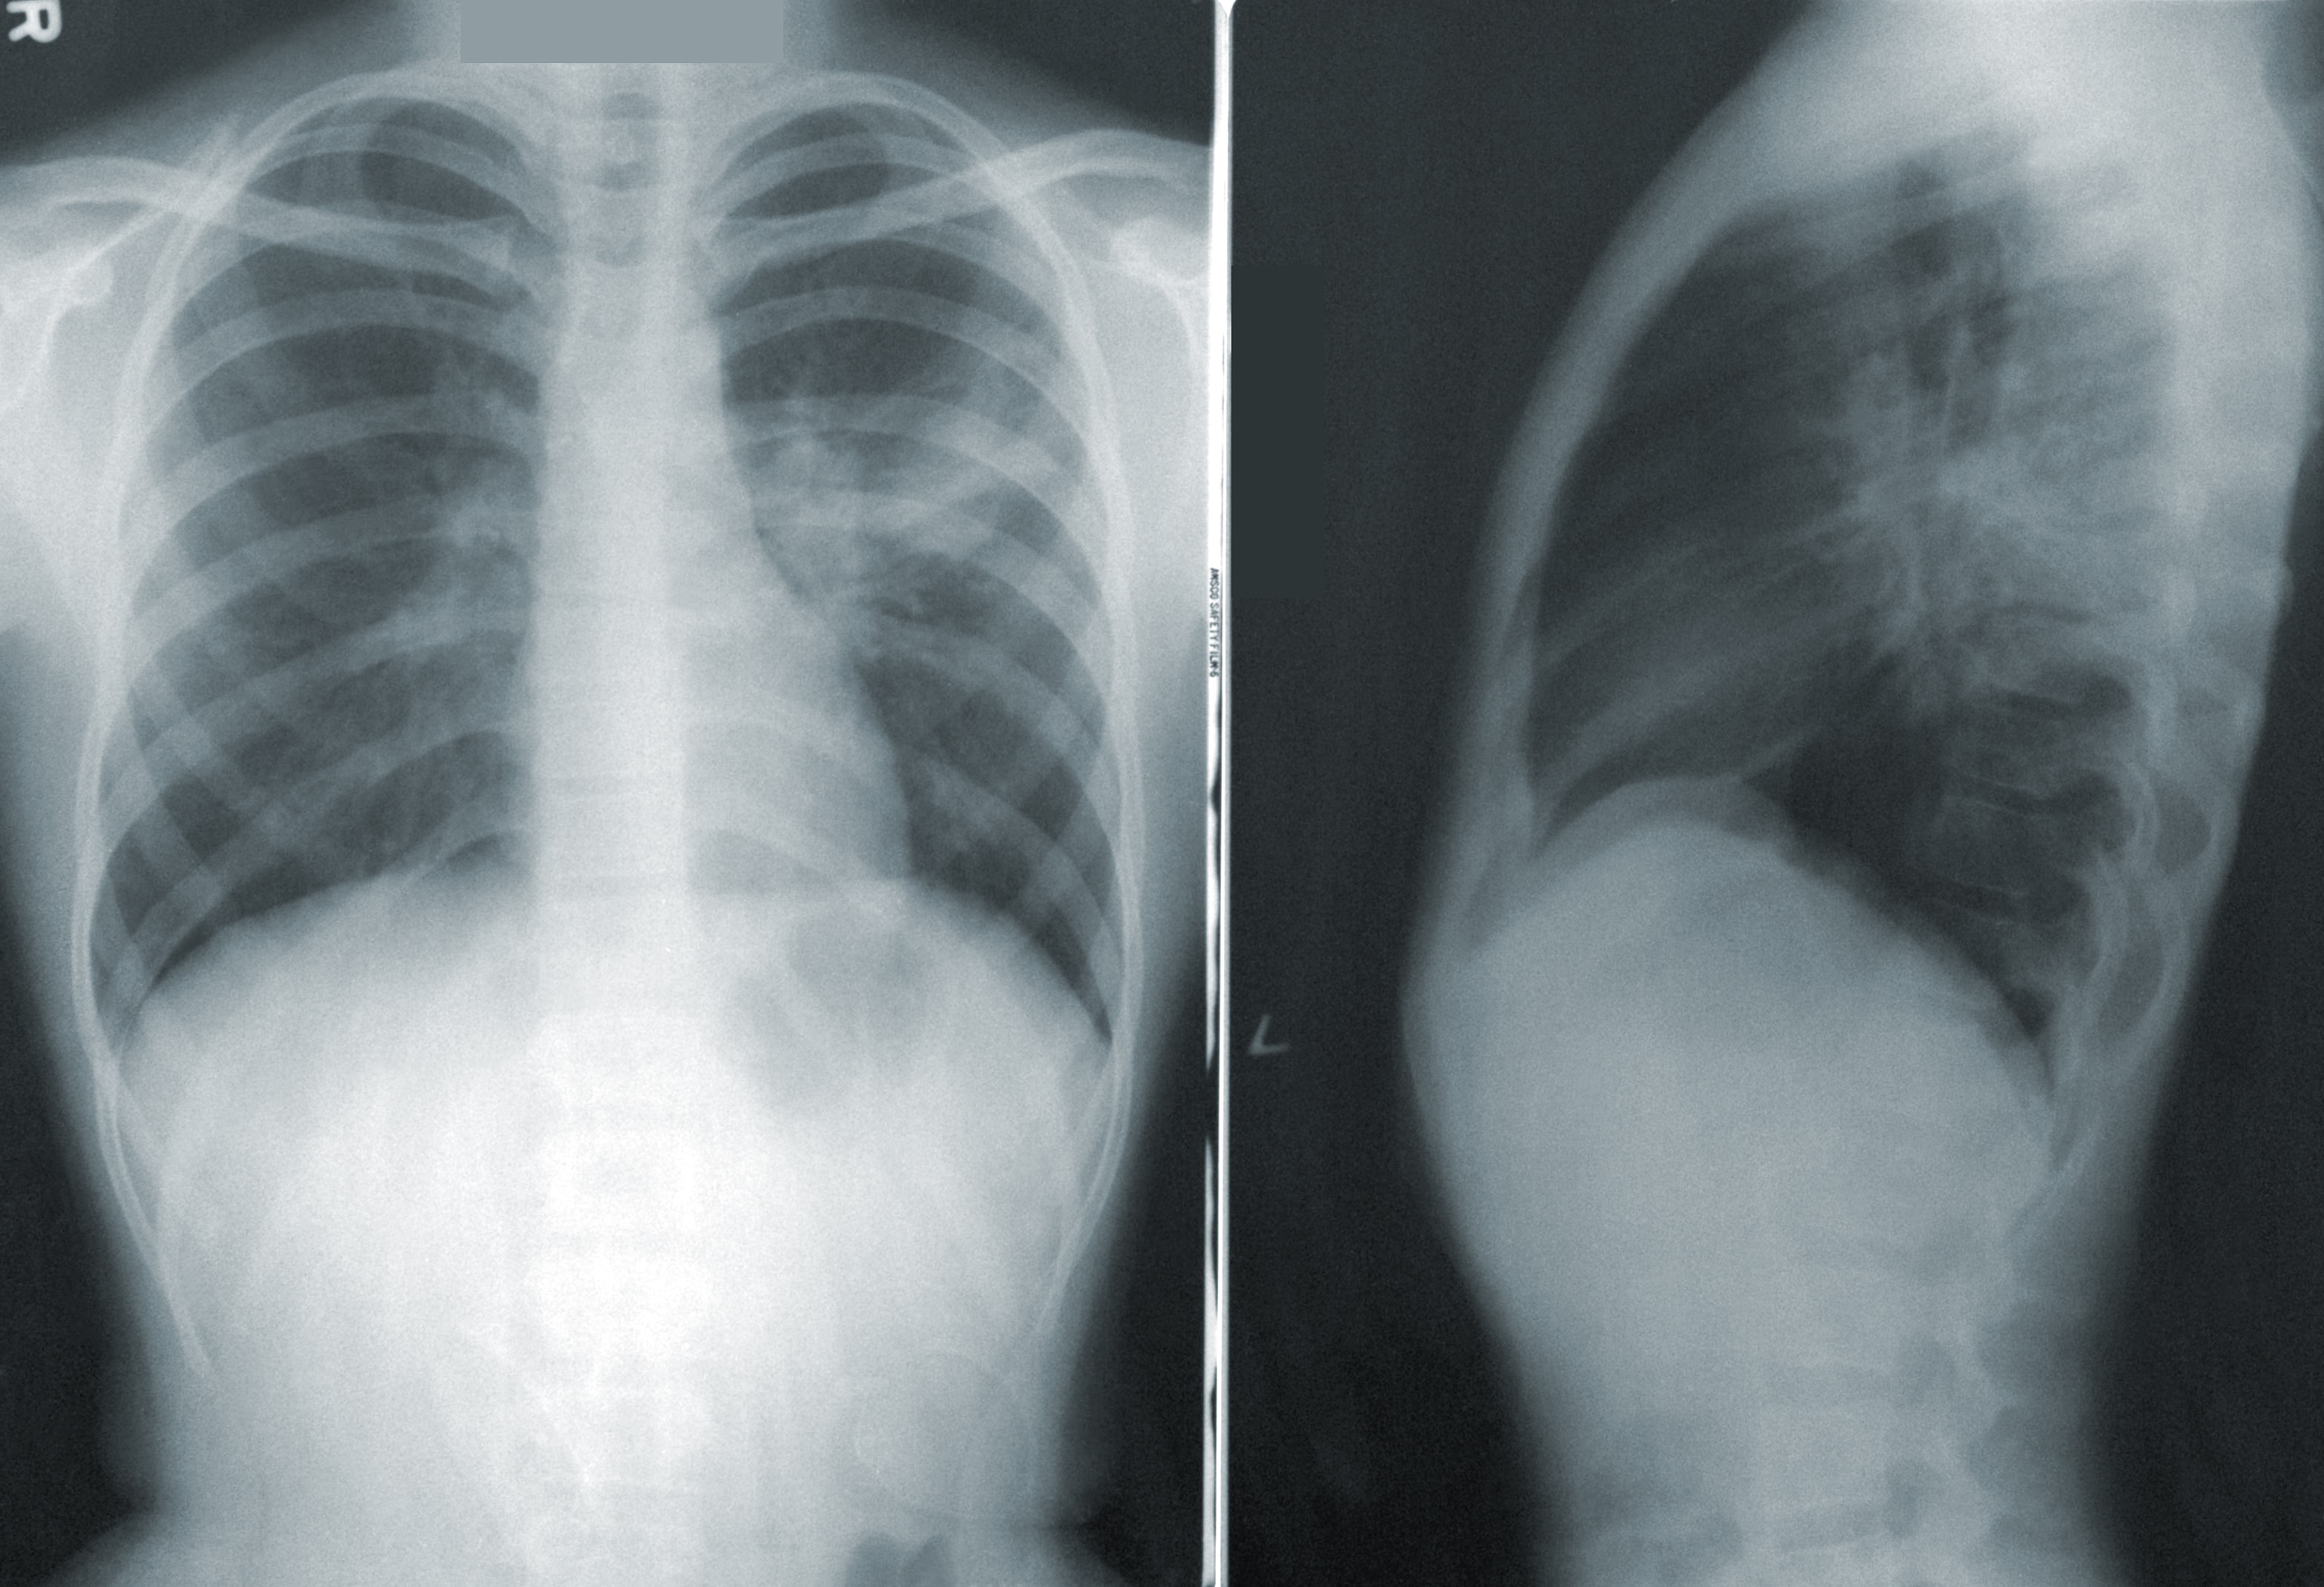

An Image classification project based on Convolutional Neural networks (CNN). The X-ray images were pre-processed and scaled using Keras preprocessing tools and were then trained on a custom CNN. A pretrained model ResNet was also used on top of the custom CNN to improve the performance of the model.